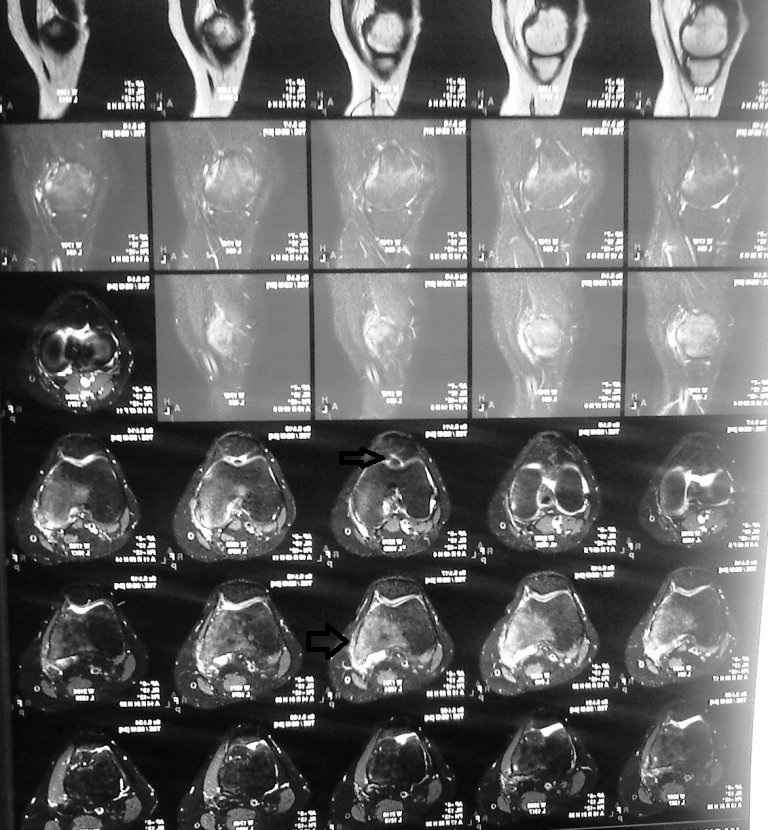

Пациентку беспокоит правый тазобедренный сустав в области вертела (именно там где имеются рентгенологические проявления . Сегодня мне были доставлены выполненное ей ранее РКТ правого коленного сустава(имеются выраженные изменения (лизис мыщелка бедра и дополнительное образование в межмыщелковом возвышении) . В биохимических анализах по ревматоидной программе изменений нет. В ОАК повышена СОЭ (29).